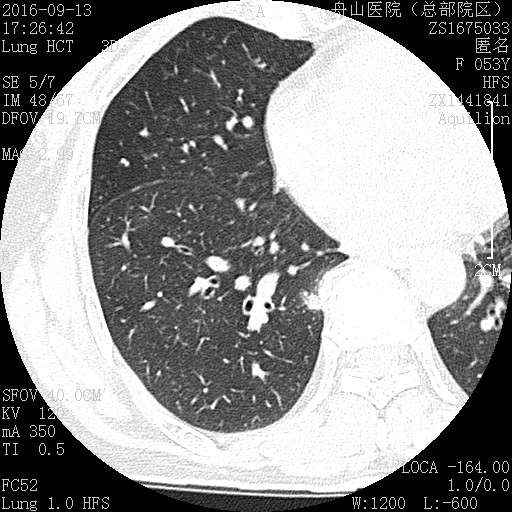

这个人的支气管腔有一大团曲霉,被冲掉了,扩张的支气管有炎症细胞浸润,还有支气管外侧,含铁血黄素沉积。

为什么有含铁血黄素呢? 曲霉菌容易使周围出现出血。太多含铁血黄素,吞不完 剩下一点曲霉菌,看看:

菌丝都快死了,隐约可见 这些红黑色点点是什么? 王:中性粒细胞,挺多的。这也是曲霉菌感染的一个特点。

刚才的曲霉菌是这里?王:是的,这里有残留菌丝 第二例曲霉

曲霉菌孢子很少见到,基本都是菌丝团,这里也是支气管扩张区,菌丝团偏黄褐色,也快死了。

蓝色圈圈是菌丝团?红色箭头是淋巴细胞?这是空腔边缘吗?王:是的,红箭头也可能是中性粒细胞。 红箭是支气管粘膜有炎症。

这里的菌丝形态清楚,下图小圆空的结构挺多,我理解为管状菌丝的断面

支气管扩张都有平滑肌增生吧?王:一般会有 王老师 ,这些是单纯HE染色还是有特殊染色?王:HE